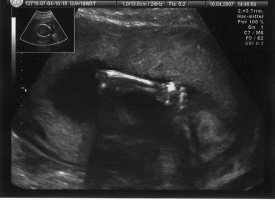

Anbei will ich euch mal zwei Fotos von meinem Krümel zeigen. Die fotos sind allerdings schon etwas älter und zwar vom lezten Artztermin am 20.03.2007

Liebe Grüße

Katzen-Engel